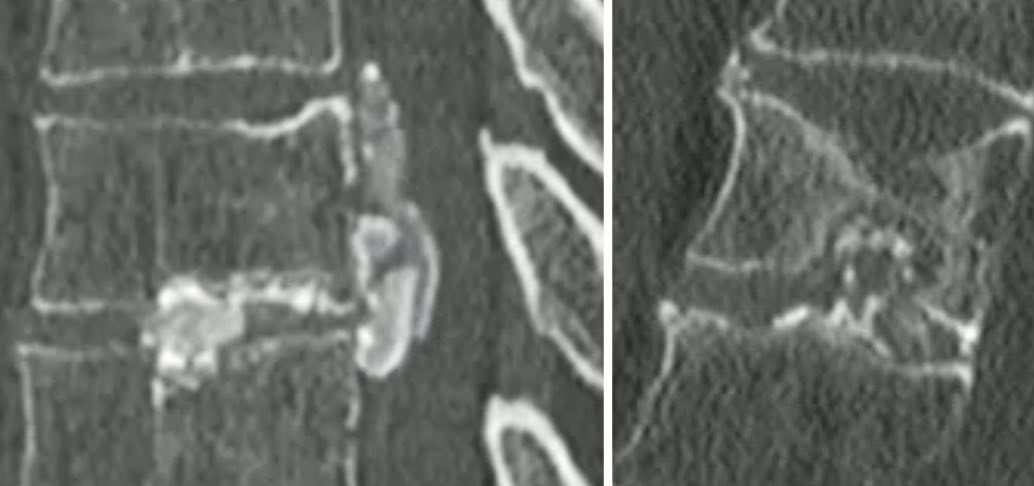

SpA

SpA ankylosante = forme axiale, H35

- sacro-iliite bilatérale (DD ostéose iliaque condensante et arthrose)

- charnière thoraco-lombaire = coins antérieurs des vertèbres (mise au carré) + syndesmophytes

- enthésopathies périphériques = tendon calcanéen++

- articulations périphériques = hanches++

Rhumatisme psoriasique = forme périphérique, début vers 40 ans

- arthrite érosive IPD (DD arthrose = ailes de mouettes)

- ostéolyse / ankylose des IPP

- périostite juxta-articulaire en bande ou en cupule

- résorption des houppes phalangiennes ou ostéopériostite de la phalange distale